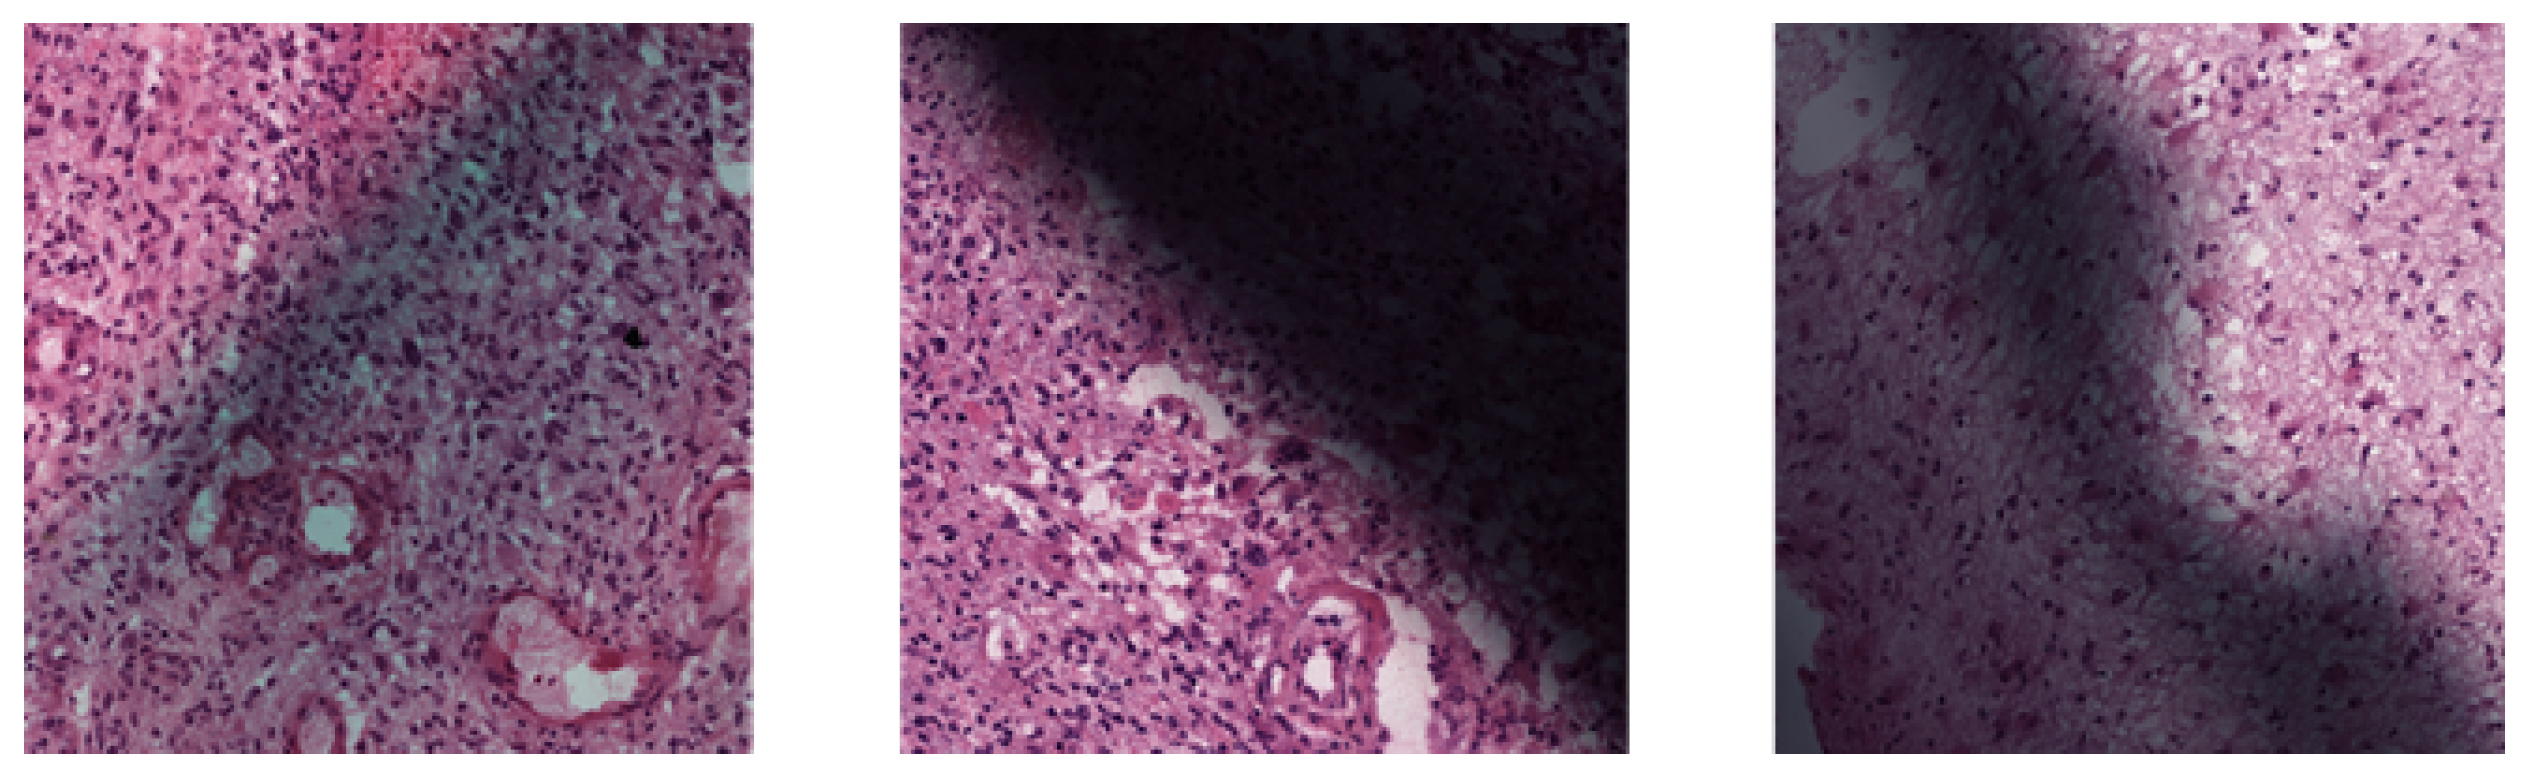

3.2.2. Artifact Detection

We observed that some WSIs provided in the dataset had marker drawings. When extracted into patches, these marker drawings covered a large area of the patches, leading to altered color or diminished contrast. To detect these affected patches, we employed the Laplacian edge detection method [16] provided by OpenCV on grayscale patch images generated using the COLOR_BGR2GRAY method [17,18] to identify edges within the patches. Regions affected by markings tend to have fewer edges detected due to reduced contrast. The variance of output images was calculated as an indicator of edge presence. Patches that had a calculated variance less than 300 were considered as affected and removed. Examples are shown in Figure 3.

Figure 3. Patches with less than 300 detected edge variance were removed.